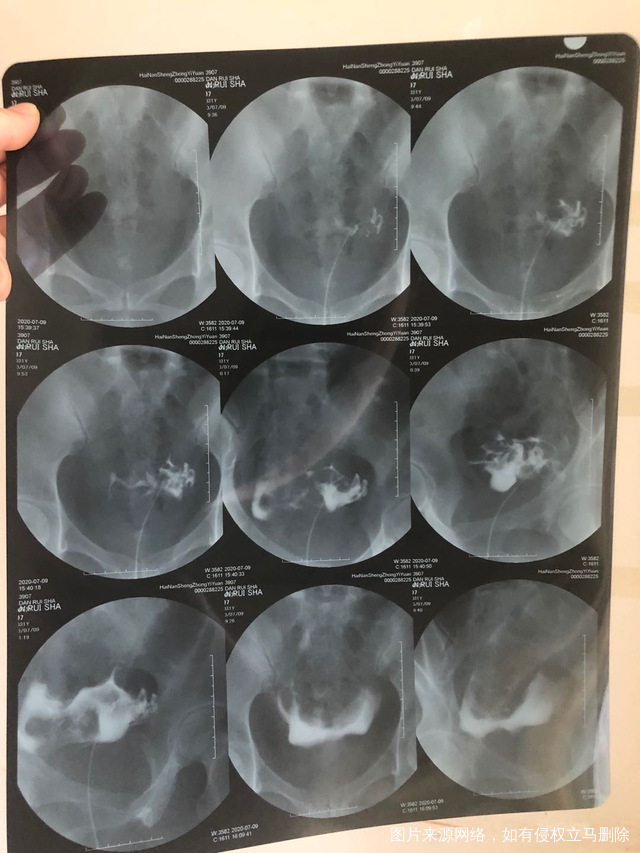

这是2020年八月份做的造影这种情况还能自己

做完输卵管造影第六天了小腹还是感觉沉甸甸的如

可以热敷腹部,如果有发热,腹痛加剧,白带量多,有异味,随时就医